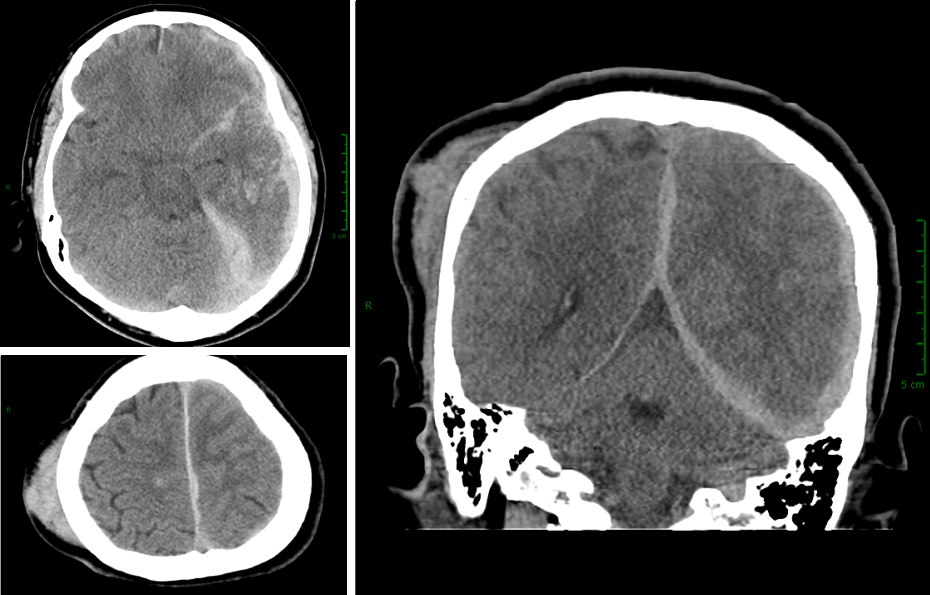

Parenchymal brain laceration with a fluid level. Case 18. A, Axial NCCT What Is A Brain Laceration Cerebral contusions are bruises of the brain, usually caused by a direct, strong blow to the head. Cerebral contusions are bruises of the brain, usually caused by a direct, strong blow to the head. Traumatic brain injury (tbi) is an injury to the brain from an external mechanical force. An object that goes through brain tissue, such as a bullet. What Is A Brain Laceration.